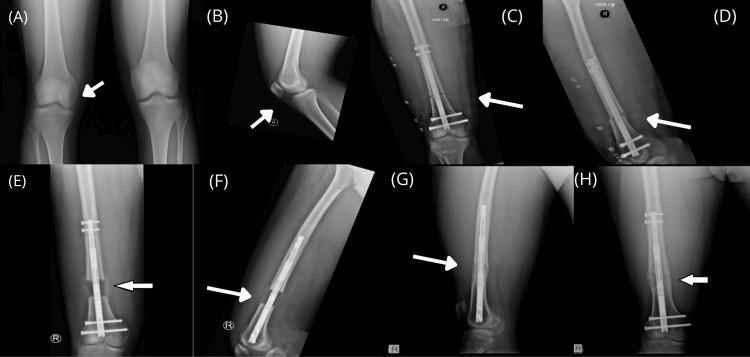

使用电动和磁驱动髓内钉治疗下肢长度差异的下肢骨延长结果。

Results of Lower Limb Bone Lengthening by Using Motorized and Magnet-Driven Intramedullary Nails to Treat Limb Length Discrepancy.

Limb length discrepancies (LLDs) can be treated with limb lengthening using external fixation or intramedullary nails, such as PRECICE or FITBONE. PRECICE is a magnetically driven titanium nail, while FITBONE is a motorized nail; both use an external remote control. This study aimed to determine the complications, compensation of length difference, time needed for compensation, and healing outcome of bone lengthening using motorized or magnet-driven intramedullary nails among non-cosmetic limb lengthening cases.

RESULTS

All patients achieved correction of their limb length without any device failure or nail breakage. The achieved limb length for all patients averaged 38.4 mm, ranging from 21 to 60 mm. No intraoperative complications were observed. Postoperatively, one patient reported knee stiffness, and another developed deep venous thrombosis. Duration of distraction (average 43.93 days, range 30-66 days) and the mean healing index was 32 days/cm for both the femur and tibia.

CONCLUSION

This study confirms that intramedullary nail PRECICE 2 and FITBONE systems are reliable and effective lengthening devices for treating lower LLDs and deformities. These devices significantly reduce complications and achieve excellent outcomes.